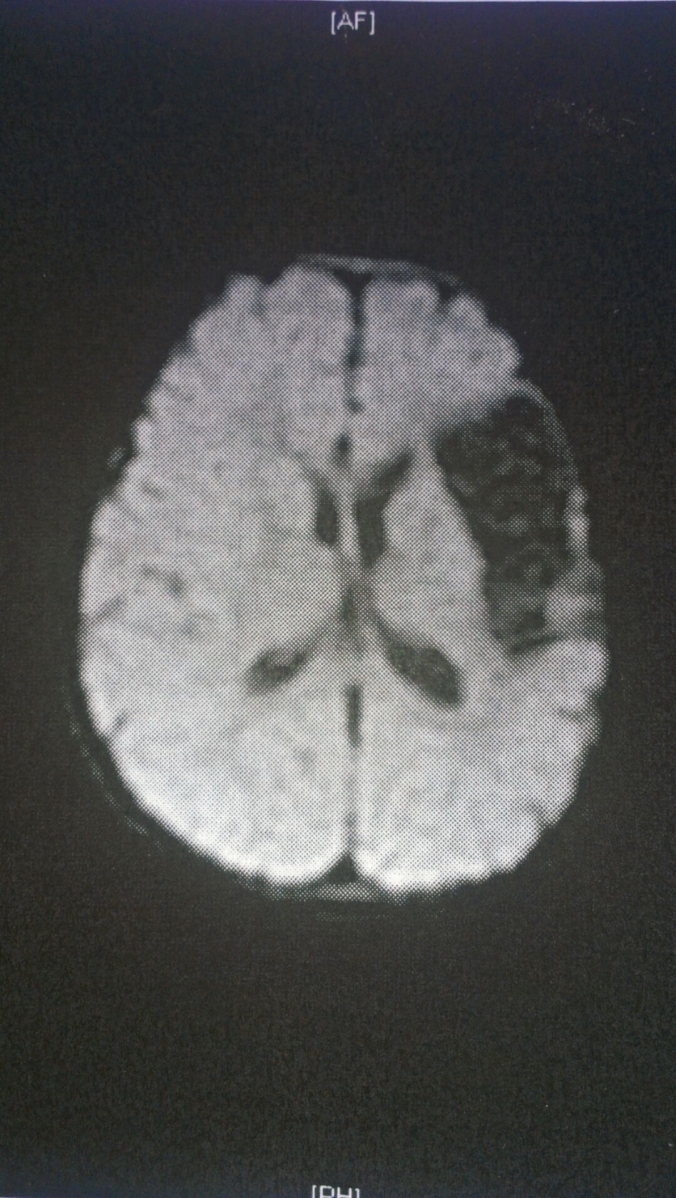

This is a brain. It is also the unfortunate outcome of a baby whose mother experimented with cocaine, resulting in a premature birth and a bleed in the baby’s brain. A bleed in the brain means the baby had a stroke. Hey! Wait a minute! Babies and strokes don’t go together, or do they?

But of the 100 or so children in the study, the researchers are working feverishly to know how stroke affects their language skills. Magnetic Resonance Imaging, most commonly known as MRI, is administered to the child to watch how stroke affects different parts of the brain. Sometimes, the brain readjusts itself, said the researchers, especially in a newborn, to compensate for the section that was harmed. Known by the medical term as plasticity, the brain takes charge of the imperfect tissue with the good part of the brain. In fact, in the first 28 days of life, stroke is more common than after.

Joey was diagnosed with left-sided hemiparesis (weakness on the left side of the body) due to a stroke in-utero. An MRI followed and confirmed the diagnosis.